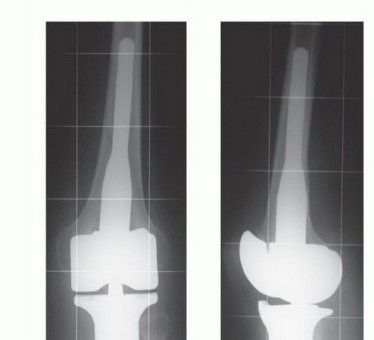

أورام قصبة الساق القريبة هي آفات عظمية معقدة تتطلب استئصالاً دقيقاً مع الحفاظ على الطرف. يشمل العلاج إزالة الجزء المصاب من قصبة الساق، ثم إعادة بناء مفصل الركبة باستخدام أطراف صناعية أو طعوم عظمية، مع التركيز على استعادة وظيفة الطرف وتقليل المضاعفات لضمان أفضل النتائج للمريض.

ومع ذلك، شهد العقدان الأخيران ثورة حقيقية في مجال جراحة أورام العظام، مدفوعة بالتقدم الهائل في تقنيات التصوير التشخيصي، والأساليب الجراحية الدقيقة، وتطور المواد المستخدمة في إعادة البناء. لم يعد البتر هو الخيار الوحيد، بل أصبح الحفاظ على الطرف (Limb Salvage) هو المعيار الذهبي للعلاج كلما أمكن ذلك، مما يمنح المرضى فرصة ثمينة للحفاظ على وظيفة أطرافهم، واستعادة حركتهم، وتحسين جودة حياتهم بشكل جذري.